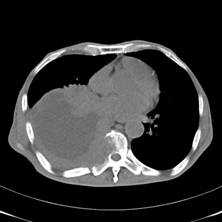

典型病例1:患者鞠xx,女,68岁,住院号:488141,因左胸痛1月余入院。2015年3月31日胸部增强CT示:左肺下叶2.5cmx2.8cm占位,左侧第三前肋骨溶骨性转移、形成厚约3cm肿块,左侧腋窝淋巴结2.1cmx4.1cm及前纵膈淋巴结转移。患者于2015年4月1日经CT引导下穿刺活检、病理证实为左肺下叶腺癌。于2015年4月5日对其采用125I放射性粒子置入治疗。治疗3个月随访,患者胸痛缓解,左肺下叶原发病灶消失,粒子聚集;左侧第三前肋骨基本恢复正常形态;前纵膈淋巴结消失,粒子聚集;左侧腋窝淋巴结缩小2/3。目前患者生活质量良好,可从事一般家务劳动。

术后三个月CT片: